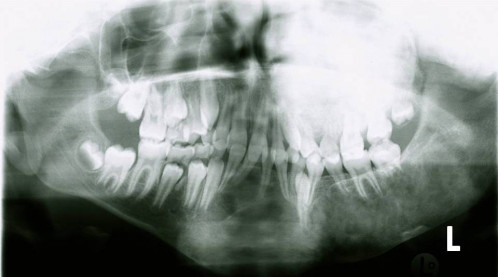

Eine 16-jährige Patientin kommt in eine MKG-chirurgische Praxis zur Abklärung der weiteren Vorgehensweise bzgl. ihrer Erkrankung.

Sie betrachten die angefertigten Röntgenbilder. Welche der folgenden Röntgenbefunde ist korrekt? Ossäre Auftreibungen im Bereich …

- A… der Mandibula links.

- B… des Os frontale links.

- C… des Os zygomaticum links.

- D… des Os temporale links.

- EAlle genannten Aussagen sind korrekt.

Bildgebung - OPAN 2004